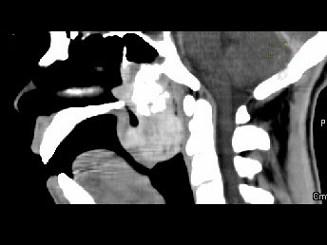

问题 男性,57岁,睡觉打鼾,近来加重,CT扫描如图所示,请选择正确的描述和答案 ( )

选项 A、考虑为鼻咽癌 B、考虑为鼻咽部多形性腺瘤 C、肿块内密度尚均匀,其上方见较多钙化影 D、肿块边缘大部清楚,邻近结构未见明显受侵 E、鼻咽腔偏右侧可见类圆形软组织块影

答案 BCDE